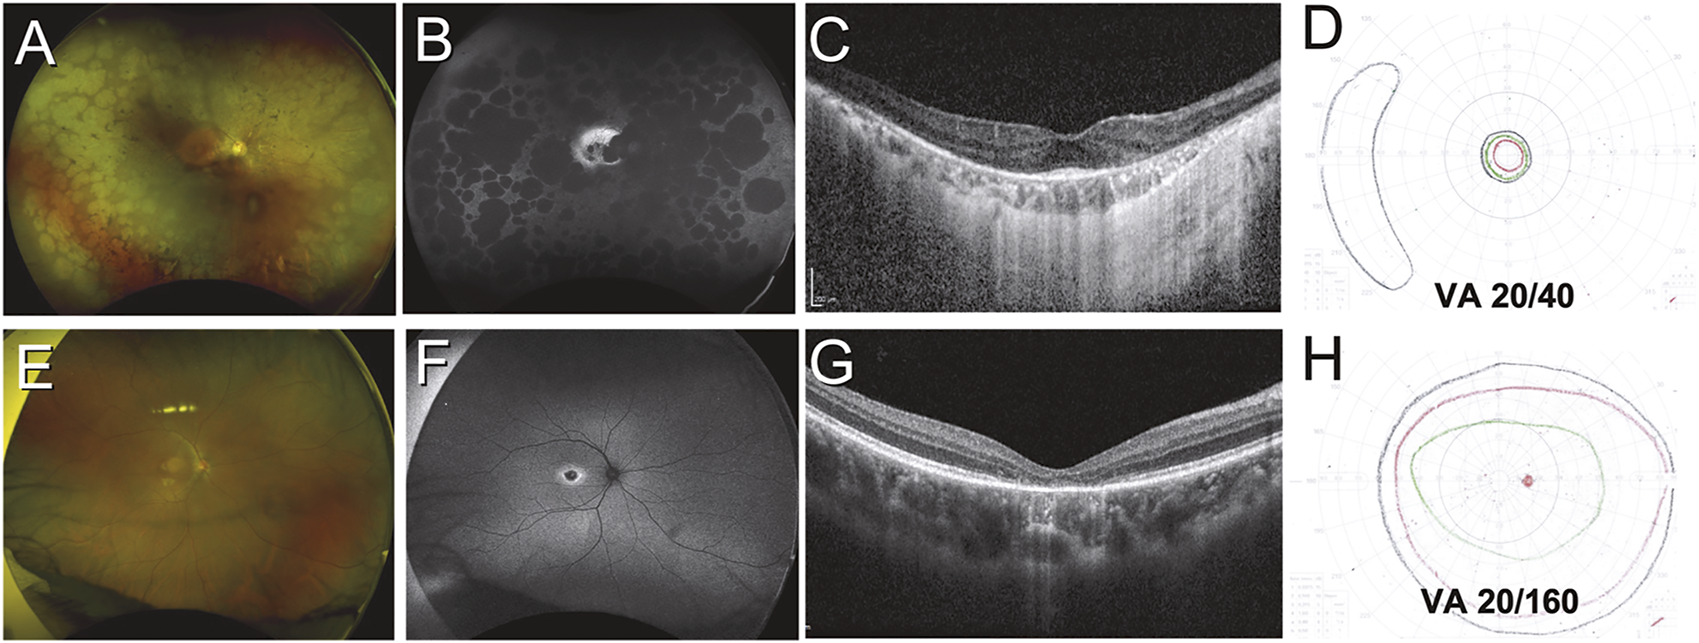

FIGURE 2

Variation in structural and functional changes due to inherited retinal disease. Case 1 (A–D) was a 51-year-old Indonesian male with retinitis pigmentosa secondary to PRPH2 mutation. Retinal findings include diffuse peripheral RPE atrophy seen on color and autofluorescent imaging (A,B) with sparing of the central macula (B) and a small focus of foveal outer retina intact on OCT imaging (C). Visual acuity was only mildly impaired, but the patient had tunnel vision as demonstrated by Goldmann kinetic perimetry (D). Case 2 (E–H) was a 21-year-old Chinese male with cone dystrophy secondary to PROM1 mutation. Retinal findings are limited to subtle pigmentary changes at the macula (E) which are highlighted on autofluorescent imaging (F), while OCT reveals loss of the outer retina at the foveal region (G). Visual fields are largely preserved but the patient had severely impaired visual acuity (H).

In contrast to RCDs, patients with cone-rod dystrophies (CRDs) present with essentially the opposite sequence of symptoms. Visual acuity, impaired color vision, and photosensitivity occur first, followed later by visual field loss and nyctalopia (Figure 2). Predictably, CRDs result in more severe visual impairment earlier on in the course of the disease, although the end-point for both RCDs and CRDs is essentially the same (Hamel, 2007).